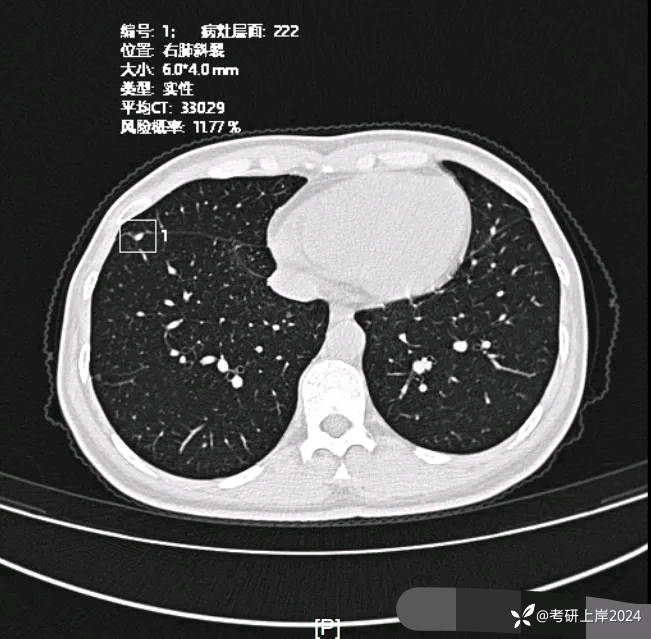

患者最近的检查有AI辅助诊断意见,找出的病灶分别如下:

病灶22:左下叶贴着叶间裂处密度偏高微小结节,良性可能性稍大,因其密度显高,轮廓与边界显糊,又在叶裂处。

病灶24:右下叶叶裂处结节,实性,边缘光滑,没有收缩力,密度过高,考虑肺内淋巴结或碳沫沉积可能性大。2023年12月最明显的结节形态:

与2024年3月份复查时的对比,几乎没有变化。我的回复:两肺多达20几处结节,除了最后一处实性的考虑良性的,其他的都是磨玻璃密度,整体轮廓较清的,这在3月份的AI诊断上都有截图,其中最主要的几处就是我另外再截图了发来的这几处。它们也仍算是磨玻璃密度,病理大概会是原位癌可能性大,个把最坏可能是微浸润性腺癌,其实说不上明显实性成分,只是右上叶的那三处,最靠纵隔的那枚有血管穿过,显得像是混合密度,但肿瘤的成分仍是磨玻璃的。鉴于多发,又无法都通过手术全部切除,我的想法仍是再观察随访为主,待主病灶进展到有风险了再来考虑干预处理主病灶,并到时候兼顾同侧的其他结节是否顺带解决一部分。目前先随访,意见供参考!感悟:今天为什么要分享其实挺常见的这种多发磨玻璃病例?我想主要是由于结友问诊了这么多医生,仍在继续问,说明她虽然这些结节目前风险不大,但对她的心理造成了很大的压力,这也是结友最常见的心理状态。我觉得心理的崩溃或不断钻牛角尖的思考或许在短期内导致的害处更甚于结节本身!她问了这么多医生,肯定大部分都认为能随访,目前也没有风险大到定得赶紧处理的病灶,但她仍在不停的问诊,总想得到更让其踏实的答案。但哪位医生能说这些不是恶性范围的呢?谁能告诉她这是正常的呢?那不可能呀!已对查出多发结节,致病因素不明、预防措施没有、切又切不光、用药也不用!你说除了正确认识它、理性面对它,你能如何?在问诊中,总是有结友问到底有没有增长1毫米?CT值有没有增加?血管有没有进入?空泡有没有?实性成分有没有以及占多少?这些作为患者自己定要去纠结有何益?能说明什么问题呢?总体上,如果像今天这位结友医院提供AI辅助诊断意见,那是大小、体积、CT值、风险程度都会列的清清楚楚。但实际上在临床工作中,医生并不必这样按数值去判断风险或决定是否手术,如果这样还需要医生干嘛,AI全部会给出意见,AI说该开刀的转给胸外科、AI说可随访的回家下次来复查、AI说有风险的去消融等等。事实上我一直认为,我们看肺多发结节,关键就抓住:1、最主要的病灶风险如何:如果主病灶仍是危险性不高能随访,那么既无必要去数一共是10处还是15处,抑或20处,都没有意义,因为反正是按时复查就行;2、不同时期影像的对比,过于细微的差别,当其不足以改变临床决策的时候,就失去了深究的意义:纯磨只需随访的,你是5毫米也好,7毫米也罢,有何相干?反正仍不需干预处理。实性结节怕它危险,但若2毫米、3毫米,连影像特征都看不明白,更不可能为了这类结节去切下来化验,那么总在担心到底良性还是恶性,会不会是小细胞癌有何用?所以我在临床工作中,基本上不在意具体大小,也不去测CT值,关注一是实性成分有没有;二是血管有没有进入以及异常增粗;三是对比最早的与最近的有没有明显变化。放平心态、理性面对,该随访时按时随访,该干预时下决心干预!